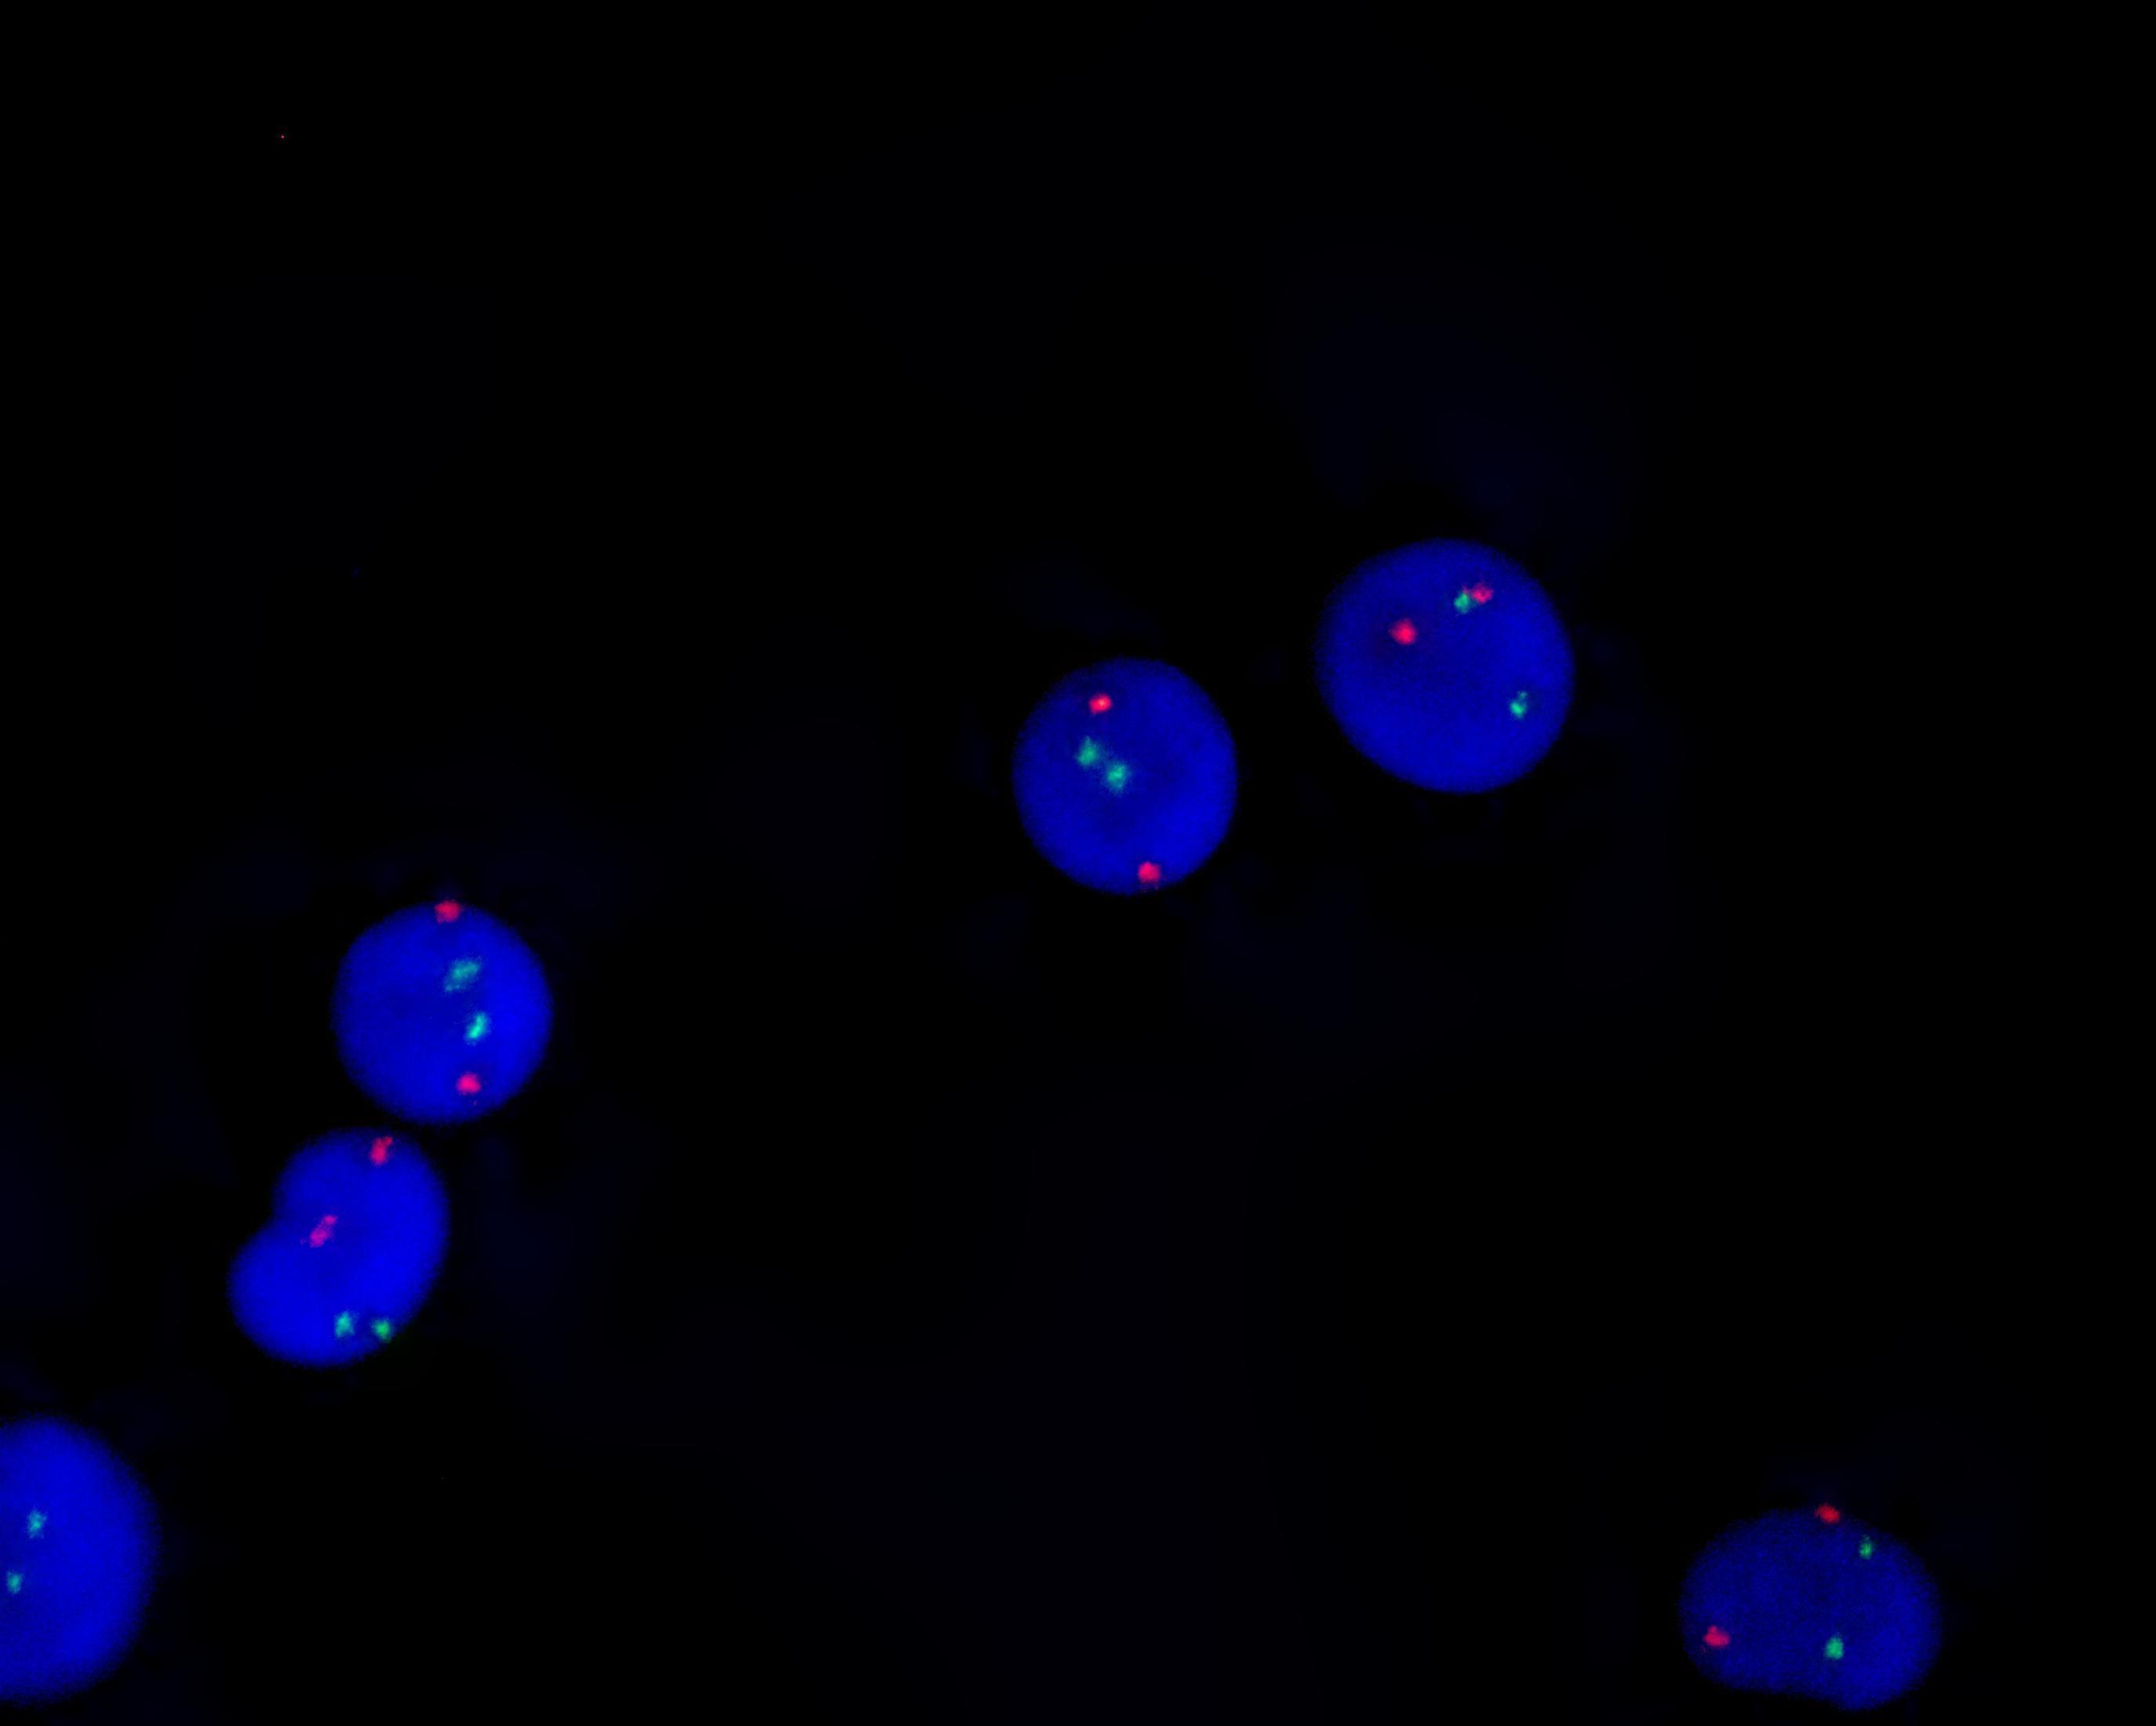

AML1/ETO gene fusion detection kit

ETO gene (8q21.3-22.1) labeled as orange, with a length of 1000 kb; AML1 gene (21q22.11-22.12) labeled as green, with a length of 1100 kb.